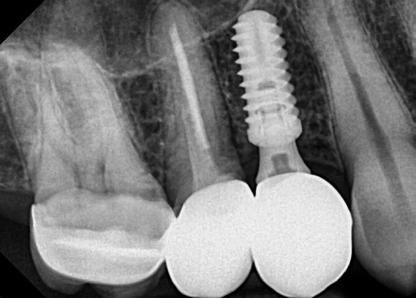

Egy fiatal páciens jelentkezett nálunk, akinek eltörött a szabad véggel rendelkező hídja (1. ábra). A hiányzó, első premoláris fog esetén implantációs pótlást javasoltunk. A csontállomány értékeléséhez CBCT-vizsgálatot végeztünk, és az elemzéséhez NNT Viewert (NewTom) használtunk, és copaSKY 4×10 mm-es (bredent medical) implantátumot választottuk a fog pótlásához

1. ábra: Műtét előtti fogászati panorámafelvétel, amelyen a hiányzó felső állcsont jobb első premolárisát és a szabad véggel rendelkező hidat láthatjuk. — 2. ábra: Az implantátum méreteinek megtervezése CBCT-vel. 3. ábra: Bukkális lágyrészdefektus. — 4. ábra: A biológiai szélesség értékelése a vertikális lágyszövetvastagság alapján. 5. ábra: Palatinális „tekercslebeny” – Palatal roll flap. — 6. ábra: Bredent medical copaSKY 4x10 implantátumbeültetés. 7. ábra: Szubkresztális implantátumbeültetés a várható biológiai szélességnek megfelelően.

(2. ábra). A lágyszövetek értékelése Seibert szerinti I. osztályú csontdefektust állapított meg (3. ábra), ezért a beavatkozáskor palatinális „tekercslebenyt” preparáltunk (palatal roll flap), és implantációt végeztünk, hogy kompenzálni tudjuk a bukkális lágyszövet-behúzódást. Megmértük a vertikális lágyszövetvastagságot, és úgy terveztük, hogy a szubkresztális implantátum beültetése összhangban legyen a biológiai szélesség kialakulásával a transzgingivális gyógyulási periódus alatt (4. ábra)